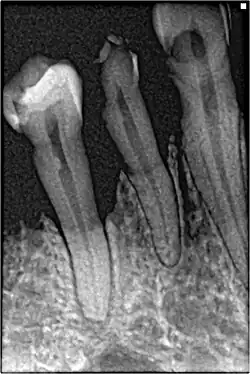

Cáncer de pulmón

Algunos tipos de cáncer se encuentran directamente relacionados con el tabaco, como es el caso del cáncer de pulmón y otros cánceres del tracto respiratorio. Esto se debe al contacto directo que presentan las células de estos tejidos con los componentes químicos presentes en el tabaco y que son perjudiciales para la salud. Sin embargo, existen otros tipos de cáncer en tejidos en los que la exposición al tabaco no es de manera directa, en este caso el desarrollo tumoral ha sido atribuido a procesos inflamatorios por depósito de partículas.[18]

El tabaco ha sido relacionado con al menos 17 tipos de cáncer, entre los cuales aparecen: cáncer colorrectal, cáncer de pulmón, cáncer de laringe, cáncer de faringe, cáncer de ovario, cáncer de cérvix, cáncer hepático, cáncer renal, leucemia mieloide aguda, cáncer de vejiga, cáncer de boca, cáncer de estómago, cáncer de esófago y cáncer de páncreas.[20] Es el principal factor de riesgo para el cáncer de pulmón, atribuyéndole entre el 80 y 85% de los casos reportados.[21]